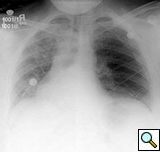

The patient’s postoperative course was uncomplicated and she was discharged on postoperative day 4. She was seen again in the outpatient clinic approximately a week later and a chest x-ray demonstrated a normal left diaphragm contour (Figure 5).